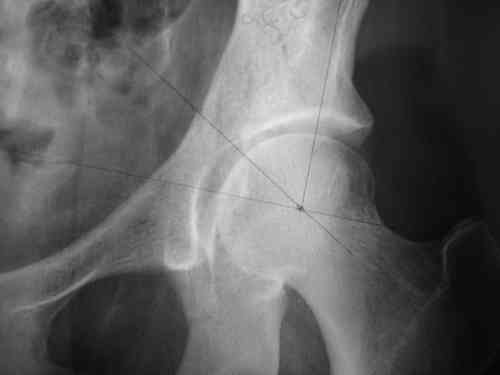

Dear group,30 years age female MVA front seat, head trauma + post column left acetabular fracture, 2.5 weeks skeletal traction. She is now conscious but still confused without any surgical treatment for brain edema.

Latest X rays and CAT is attached.Fracture within first 1.5 cm from the weight bearing dome, although AP and Obtrator oblique good, iliac oblique view reveals some displacement.I'm not sure that nonsurgical treatment will be OKHüseyin DemirorsBaskent UniversityDept of Orthopedics and TravmatologyAnkara TURKEY

My vote, given the amount of displacement on the iliac oblique and CT scan, would be for ORIF thru a posterior approach ASAP - these get pretty tough

I may get beat up for this, but I see very little displacement that concerns me on the CT. The radiograph is more concerning. I suspect it could look better, and the gap made smaller on CT. Not sure if it will affect outcome. I might give it a shot and try to see what could be done.